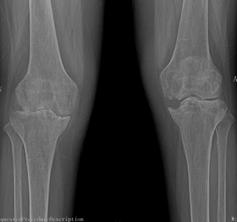

2015年10月,我院骨科二區(qū)迎來了62歲的李姓患者,她是一名類風(fēng)濕性關(guān)節(jié)炎的患者,病程10年。10年前,她被查出患有嚴(yán)重的類風(fēng)濕性關(guān)節(jié)炎,全身多處小關(guān)節(jié)疼痛,自那以后,患者就長(zhǎng)期依靠激素來控制病情。2年前,患者雙側(cè)膝關(guān)節(jié)開始出現(xiàn)疼痛、腫脹,起初還能下地走200米左右,后來走50米都感覺費(fèi)力,雙下肢膝關(guān)節(jié)出現(xiàn)變形,靠鎮(zhèn)痛藥物才能入睡。起初患者認(rèn)為,類風(fēng)濕關(guān)節(jié)炎是自己的老病,沒得治,拒絕來醫(yī)院就診。最后,實(shí)在痛苦難忍,遂在家人的陪伴下來到我院骨科二區(qū)就診。

來院后,骨科二區(qū)唐雄主任、廖浩主治醫(yī)師熱情接待了她。經(jīng)查,患者為嚴(yán)重的類風(fēng)濕性關(guān)節(jié)炎導(dǎo)致的雙膝關(guān)節(jié)破壞,雙膝關(guān)節(jié)內(nèi)翻畸形并嚴(yán)重的骨質(zhì)缺損,同時(shí)由于患者長(zhǎng)期服用激素類藥物,其全身骨質(zhì)均有嚴(yán)重的骨質(zhì)疏松?;颊叩弥∏閲?yán)重性后,感到失望、沮喪,唐雄主任信心滿滿地安慰道,“您這種情況行膝關(guān)節(jié)置換術(shù),就能徹底解決關(guān)節(jié)疼痛和雙膝關(guān)節(jié)不能活動(dòng)的問題?!庇谑牵∪擞种匦氯计鹆藢?duì)生活的希望,并要求盡快進(jìn)行手術(shù)治療。